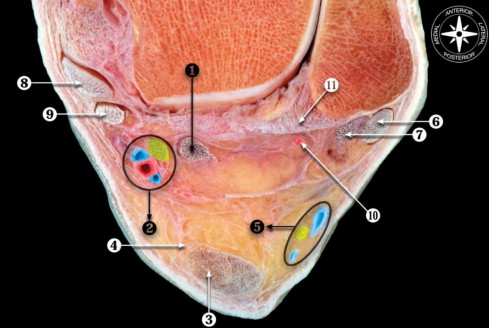

解剖